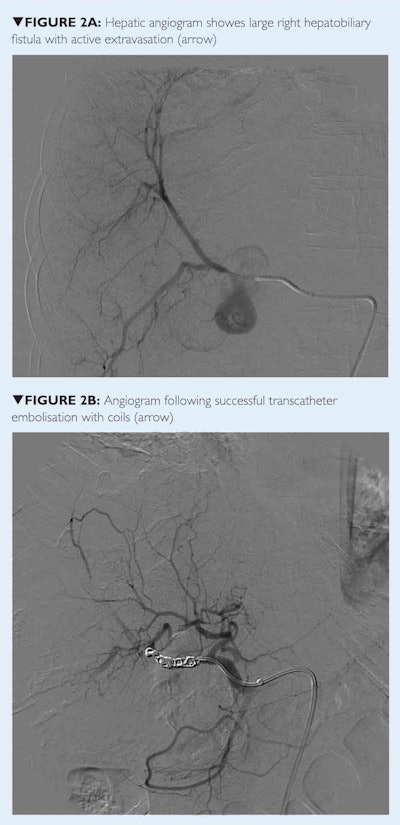

With appropriate shielding, a selective hepatic angiogram was performed that showed brisk active extravasation from the proximal right hepatic artery, just distal to the origin of the middle hepatic artery. The remaining arterial branches were unremarkable. Operative repair was deemed infeasible by the hepatobiliary surgeon. Therefore, transcatheter arterial embolization (TAE) was performed using Gelfoam and microcoils.

A postembolization angiogram showed complete occlusion of the right hepatic artery with no evidence of active extravasation remaining and the patient stabilized. The following week she underwent a cholecystectomy, extrahepatic bile duct excision, intrahepatic stone removal, and hepaticojejunostomy.